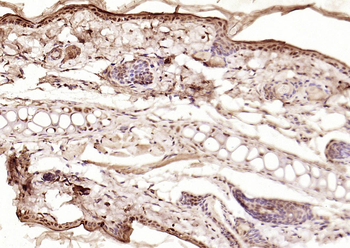

100 μl, 200 μl, 50 μlSMAD7 Rabbit Polyclonal Antibody [orb500819]

FC, ICC, IF, IHC-Fr, IHC-P, WB

Bovine, Porcine

Human, Mouse, Rat

Rabbit

Polyclonal

Unconjugated

100 μl, 200 μl, 50 μlPhospho-Smad3 (Ser213) Rabbit Polyclonal Antibody [orb106193]